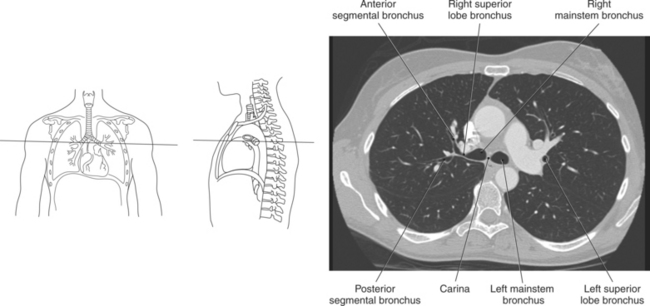

The trachea bifurcates into the left and right mainstem (primary) bronchi at approximately the level of T5. This location is commonly referred to as the carina (Figure 6.9). The right main bronchus is wider, shorter, and more vertical in orientation then the left. At the hilum the mainstem bronchi enter the lung and divide into secondary or lobar bronchi. Secondary bronchi correspond to the lobes of the lungs, thus with three divisions on the right (superior, middle, inferior) and two divisions on the left (superior and inferior) (Figure 6.9, and 6.18 through 6.20). There is further division of the secondary bronchi into tertiary or segmental bronchi that extend into each segment of the lobes (bronchopulmonary segments) (Figure 6.21 and Table 6.1). There are typically 10 segments within each lung. Each bronchopulmonary segment is functionally independent and can be individually removed surgically. The bronchial tree continues to divide many times into smaller bronchi, then into bronchioles (Figure 6.22). Each bronchiole continues to divide until it reaches the terminal end as alveoli, which are the functional units of the respiratory system. Gaseous exchange between alveolar air and capillary blood occurs through the wall of the alveoli.

Throughout its course in the mediastinum, the trachea runs anterior to the esophagus. In cross section, the trachea appears as a round air-filled structure to the point at which it bifurcates at the carina (Figures 6.9 and 6.18). The esophagus appears as an oval-shaped structure that descends through the diaphragm to enter the stomach at the gastroesophageal junction (Figures 6.27 and 6.28).